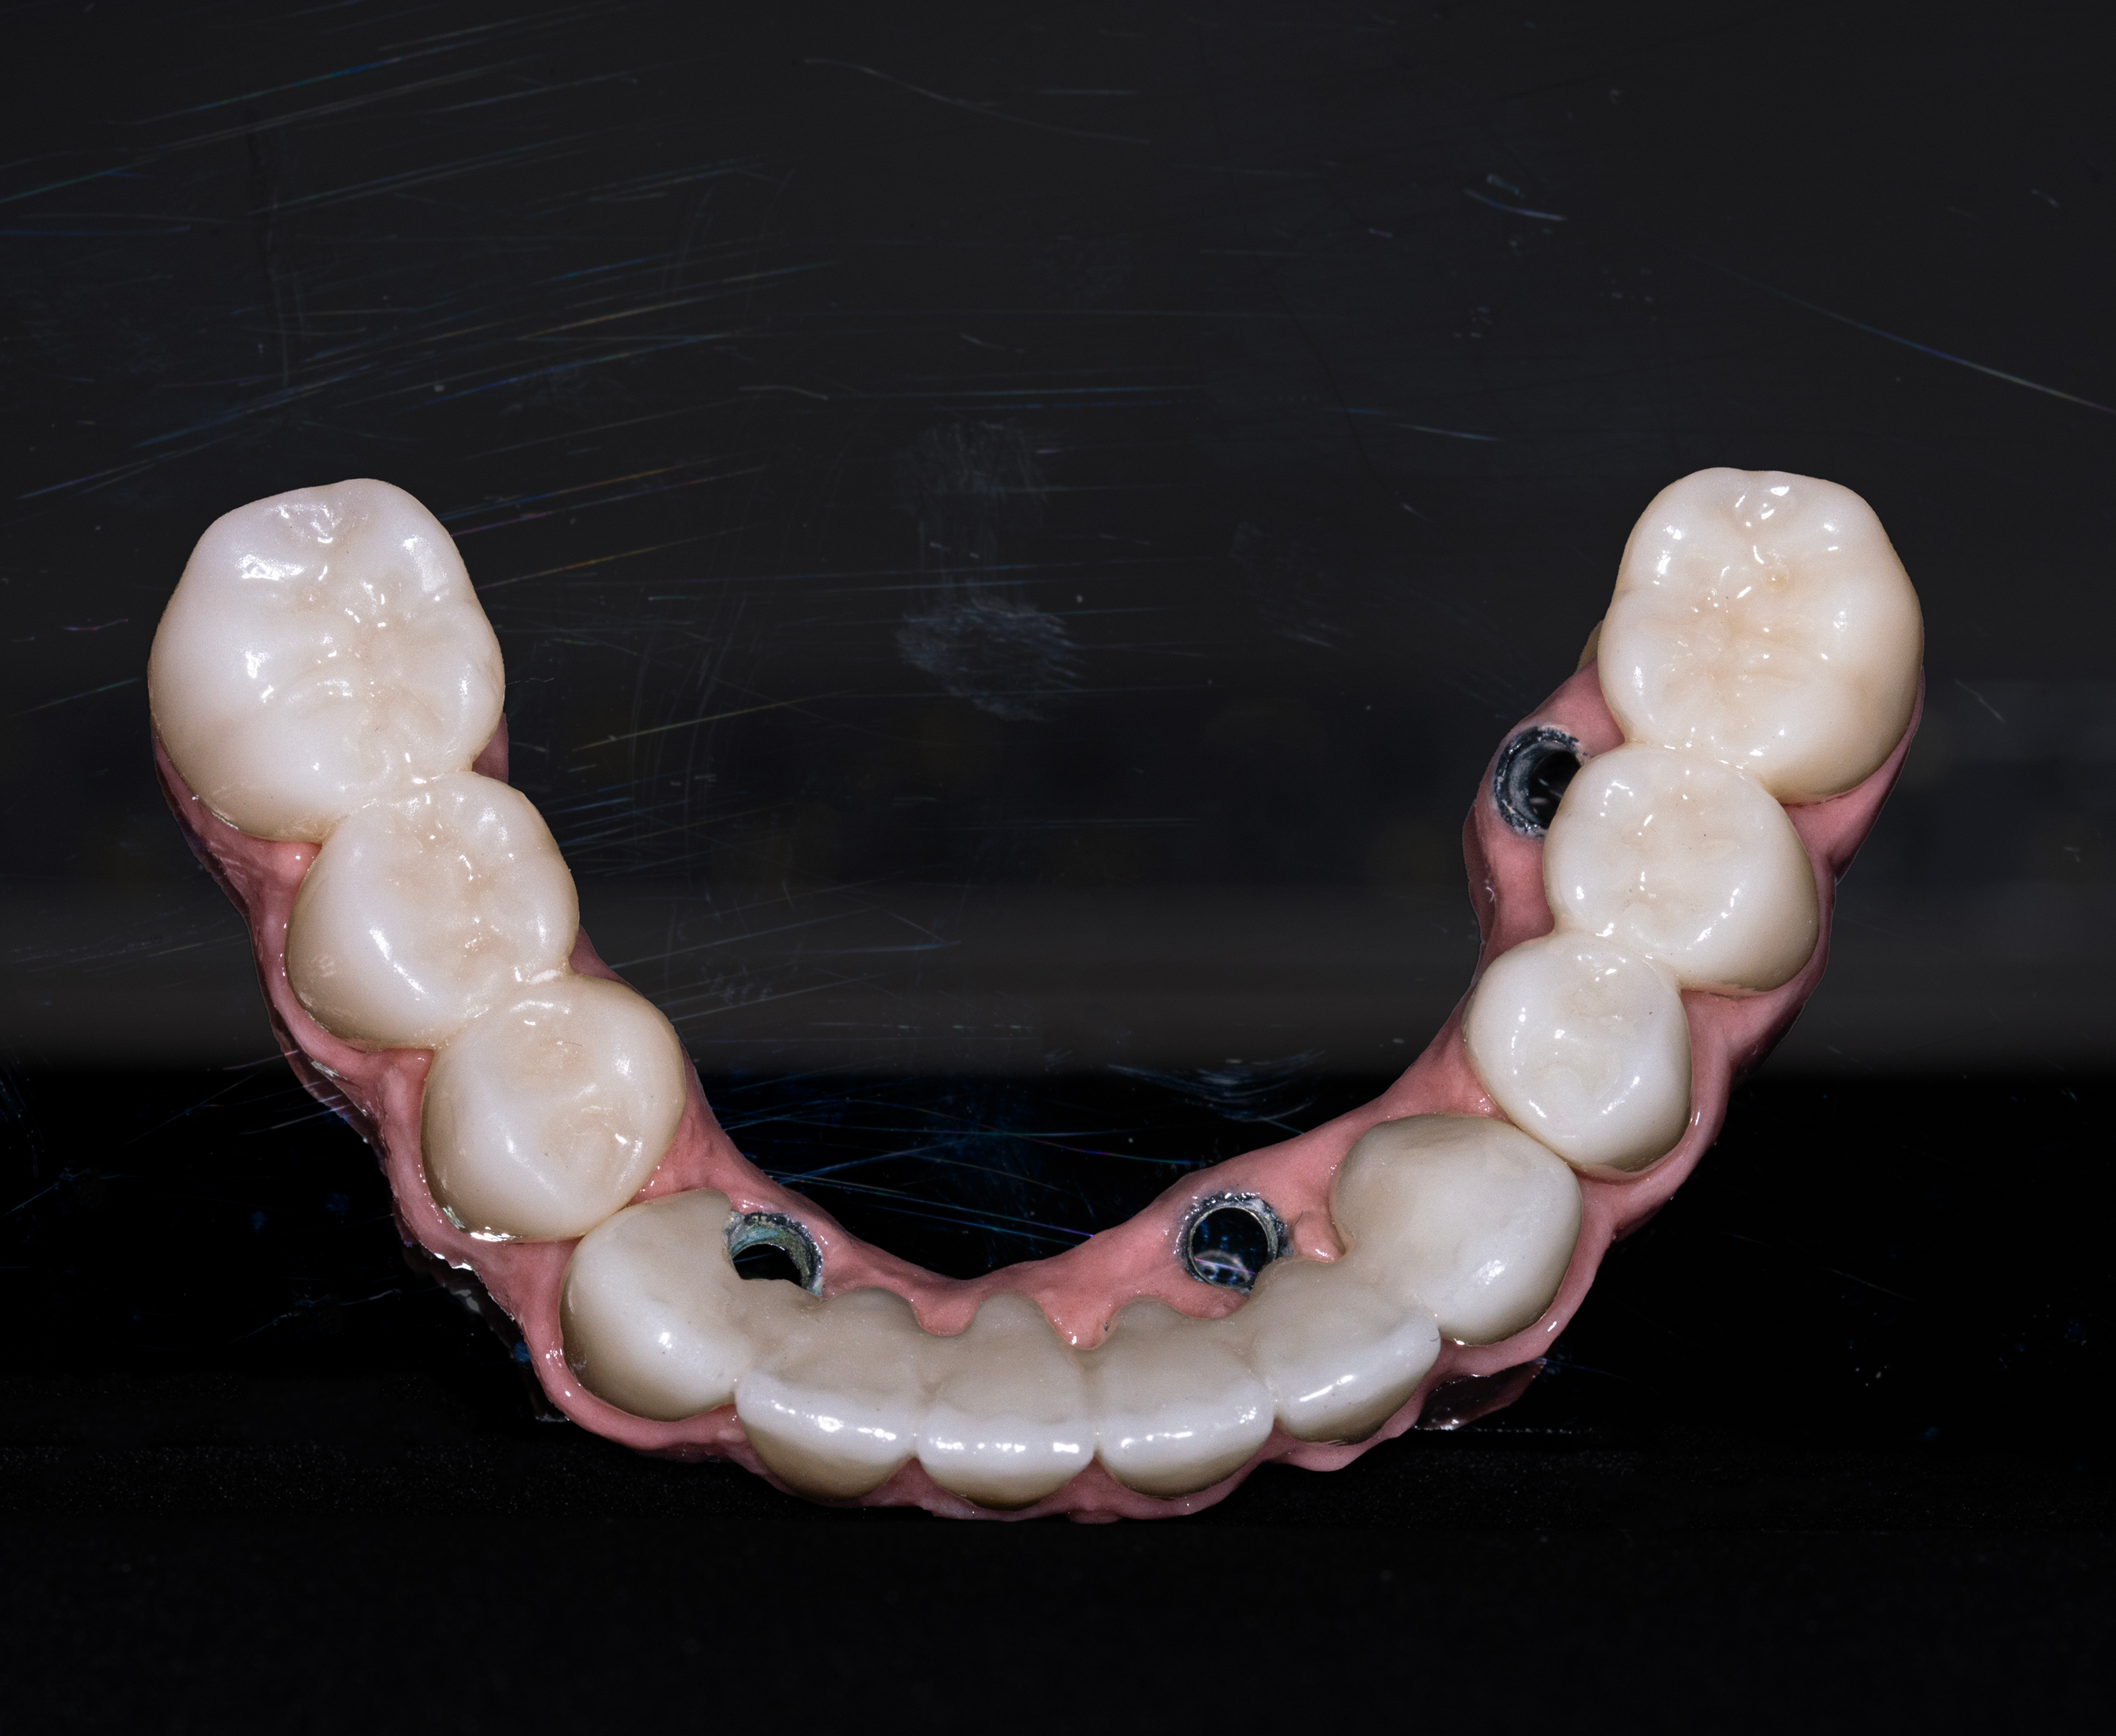

- Lower Jaw – Full-Arch Implant Rehabilitation (5 Days)

- Andrew’s lower jaw was restored using the All-on-4 concept, offering immediate function and stability.

- Placement of four strategically positioned implants

- Achieved strong primary stability, suitable for immediate loading

Day 5 — Final Fitting of Immediate Prosthesis

- Secure placement of temporary full-arch teeth

Within five days, Andrew received a fully functional lower-arch implant restoration, while his upper teeth were preserved and renewed with advanced restorative care.